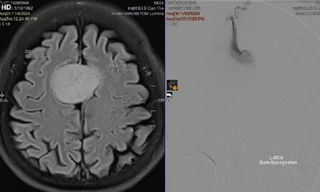

TPO - Ngày 26/11, BS Nguyễn Quang Hưng, Đơn vị Ngoại Thần kinh, Khoa Ngoại tổng hợp Bệnh viện Đa khoa S.I.S Cần Thơ cho biết, tại đây vừa can thiệp loại bỏ khối u não kích thước lớn cho bệnh nhân. Đây là trường hợp rất hy hữu, người bệnh tình cờ phát hiện khối u khi kiểm tra chấn thương vùng đầu sau tai nạn giao thông.